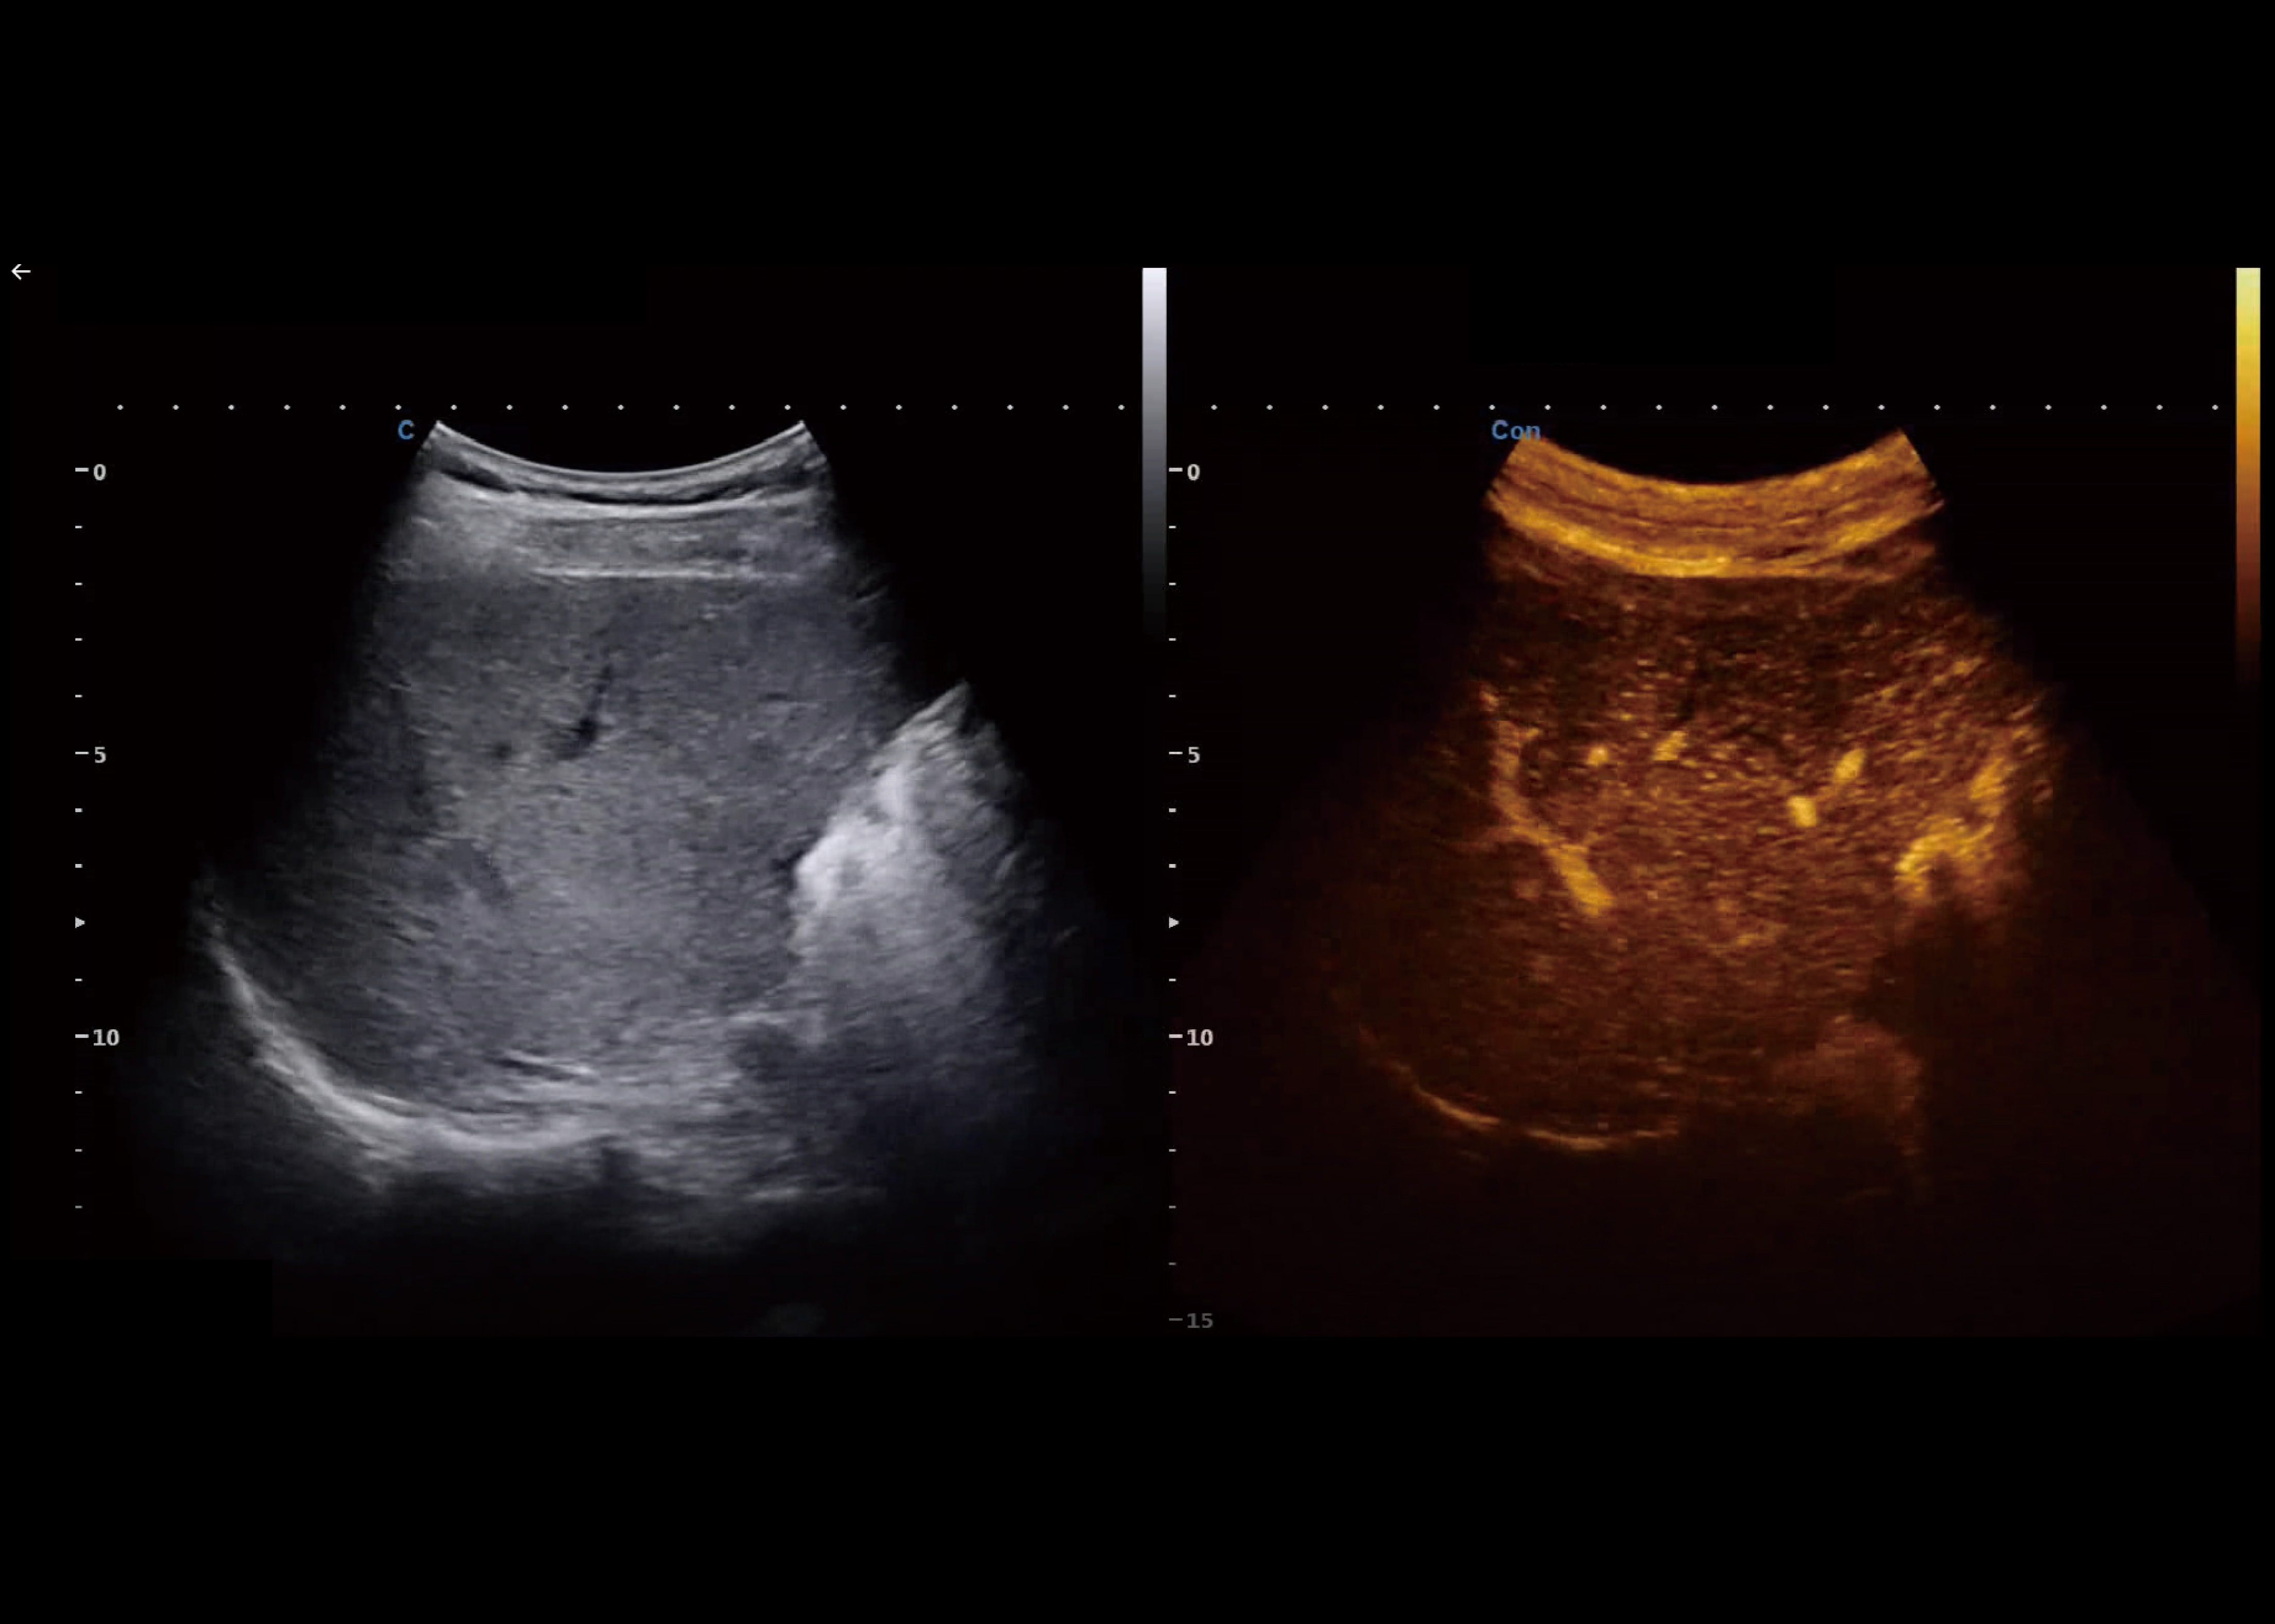

SonoContrast

● Wurde entwickelt, um die Mikrozirkulation zu visualisieren im Gewebe, d. h. der Blutfluss in nicht wahrnehmbaren Blutgefäßen.

● Potenziell für eine verbesserte Diagnose und Therapie bei verschiedene klinische Situationen

● Mehr Empfindlichkeit, bessere Leistung.

MVI

● Dabei wurde ein völlig neuer Algorithmus zur Überprüfung des Blutflusses angewandt.

● Deutliche Verbesserung der Visualisierungssensitivität bei niedrigen Geschwindigkeiten und kleine Blutgefäße.

● Mehr und genauere Informationen über den Blutfluss für die Klinik bereitstellen.